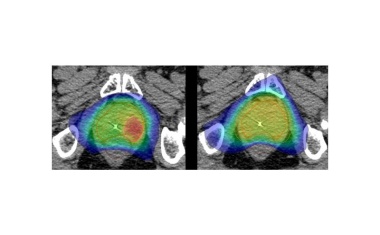

Hypostat-III-Studie startet: Verkürzte CyberKnife-Behandlung bei Prostatakrebs

Die Hypostat-Studienreihe des UKSH erforscht eine besonders schonende, hochpräzise Bestrahlungsmethode für Prostatakrebs: die CyberKnife-Radiochirurgie.